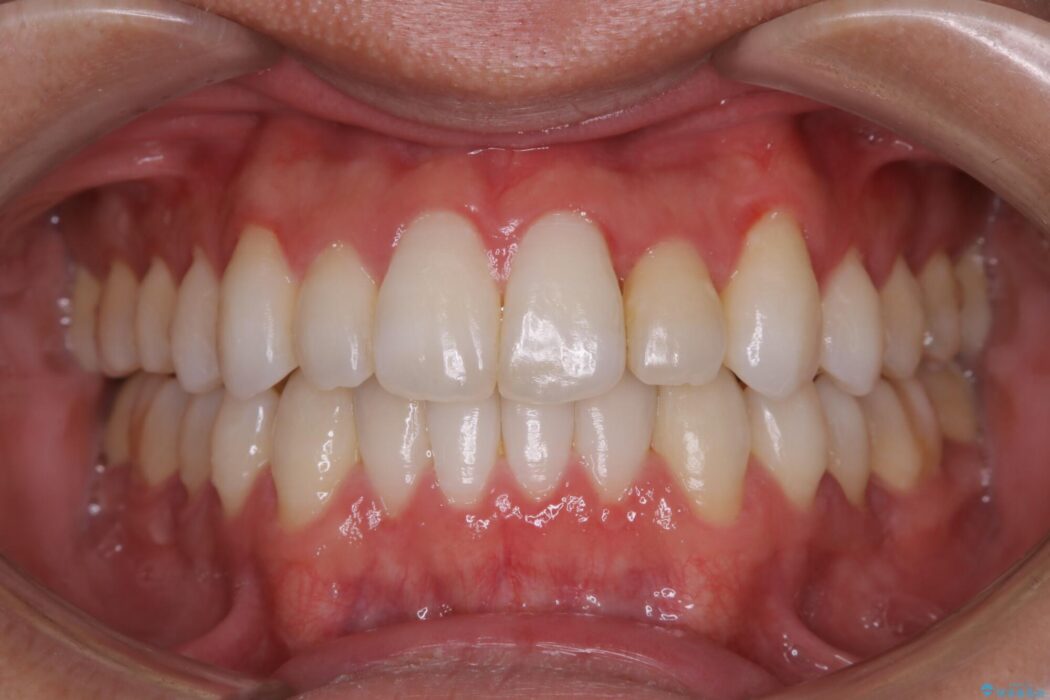

前に出ていた前歯や目立つ八重歯(3番目の歯)もきれいに並び、奥歯の虫歯治療も並行して行ったため、機能面でも見た目的にも良くなり満足していただきました。

本症例では上記3つの方法を複合的に組み合わせた治療を行いました。